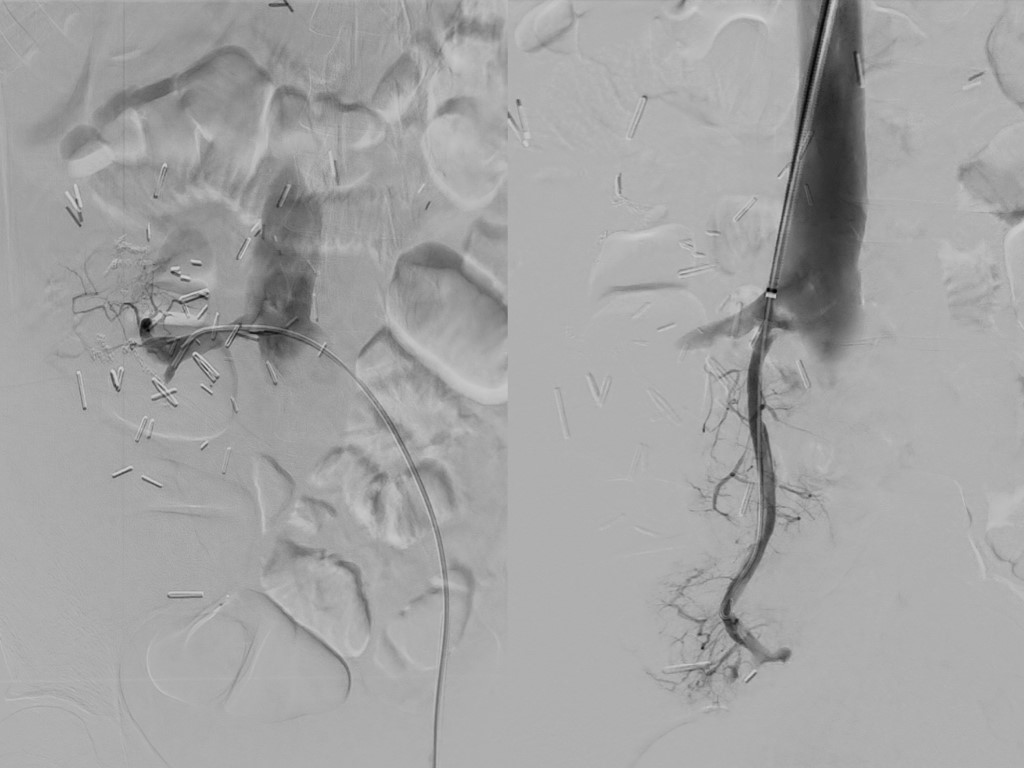

Case Report: A 20-year-old woman with an history of total pancreatectomy performed previously in 2015 for a giant solid pseudopapillary neoplasm was placed on the national waiting list for a pancreas transplant alone (PTA) in 2020 after completing 5-years of oncology follow up. The patient underwent a deceased-donor PTA in October 2022. Pancreatic venous drainage was achieved with primary anastomosis of the donor’s portal vein to the recipient's inferior cava vein, with no venous extension graft. Following our protocol, doppler ultrasonography was performed on the 1st postoperative day, revealing partial thrombosis of graft’s splenic vein. She was placed on continuous heparin infusion with no progression of splenic vein thrombosis. She was discharged on the 8th postoperative day with rivaroxaban plus aspirin. However, 30 days after pancreas transplant, she presented abdominal pain and increased amylase level. Computer tomography angiography revealed complete splenic vein thrombosis and partial portal vein thrombosis. Direct venography was performed through the internal jugular vein. Percutaneous mechanical thrombectomy was performed using Angioject catheter (6F hydrodynamic device). The lysis of the thrombus and restoration of flow in the splenic vein and portal vein was documented on immediate follow up direct venography.